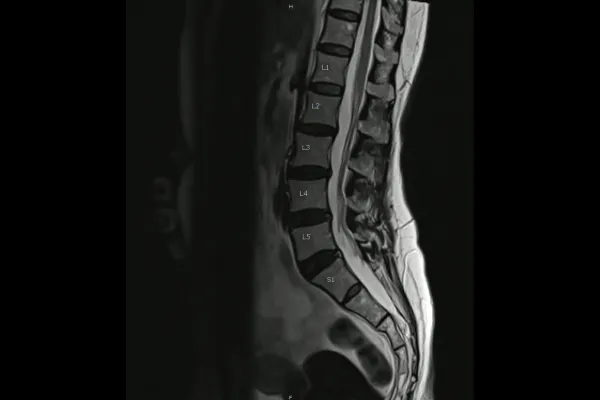

Diagnostic imaging, whether MRI, CT, or standard X-ray, is extraordinarily good at what it was built to do. It finds tissue damage. Disc herniations. Fractures. Tumors. Structural pathology that requires medical intervention.

But here is what it was never designed to capture: the way your body moves, loads, and compensates as a living system. A still image of your spine tells you what the architecture looks like in a lying-down or standing position at one moment in time. It does not tell you how that architecture behaves under the demands of your actual life.

It does not show where a spinal segment has lost its normal motion. It does not reveal how a restriction in one area has shifted load to the joints above and below it over months or years. It does not capture the compensation pattern your nervous system has quietly built around a subluxation that has been active far longer than the pain has.

Research supports this consistently. A landmark study published in the New England Journal of Medicine found that a significant percentage of people with no back pain at all showed disc bulges, protrusions, and degeneration on MRI. A 2015 systematic review in the American Journal of Neuroradiology confirmed that imaging findings commonly considered abnormal are present in large proportions of pain-free individuals across all age groups. And a 2019 study in the Journal of Orthopaedic and Sports Physical Therapy documented that movement dysfunction and altered motor control patterns are poor predictors of imaging findings in chronic low back pain populations.

Gonstead chiropractic uses full-spine, weight-bearing X-ray analysis as part of its assessment. This is not the same type of imaging ordered for pathology screening. The purpose, the positioning, and the interpretation are different.

A Gonstead structural X-ray is taken with you standing, under the load of your own body weight, in the posture your spine actually holds day to day. It is a full-spine view that allows us to see how your spinal architecture is distributing that load from the base up.

We are looking at disc space height and how it changes from one level to the next. We are looking at vertebral alignment and rotation. We are looking at the angle of the pelvis and how it influences the segments above. We are looking at the cumulative effect of compensation patterns that have developed over time.